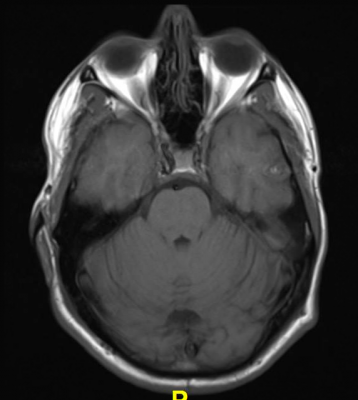

Because conventional tests such as clinical magnetic resonance imaging (MRI) brain scans and electroencephalograms (EEGs) are usually normal in patients with FND, there are currently no brain-based markers for this disorder and diagnoses are made using physical examination signs. More precise research-based imaging methods such as functional MRI and quantitative MRI have revealed several differences in the brains of some patients, including in gray matter regions. To look for any differences in the brain's white matter — which is composed of bundles of axons coated with protective myelin to help conduct nerve signals--investigators used a technique called diffusion tensor imaging (DTI), which measures the diffusion of water molecules.

The team used DTI to examine the brain white matter of 32 patients with FND and 36 healthy controls. Patients also provided information on the severity of their symptoms, the extent of the physical disability they experience, and the duration of their illness.